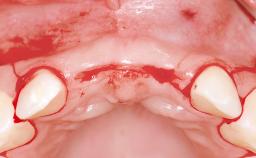

This 20-year-old woman was referred to our department in July 2006. Four months earlier, she had experienced dental trauma to the anterior maxilla when traveling in South America. The emergency treatment included emergency root canal treatment of teeth 12 and 11. Tooth 21 was also subjected to endodontic treatment later. At the initial examination, the patient was not in pain but reported increased mobility of tooth 12. The clinical examination revealed a high smile line, medium thickness of the soft tissue, and rectangular tooth forms. Discoloration of tooth 12 was evident. The periapical radiograph provided by the referring dentist indicated a fracture line at both teeth 12 and 11. A cone-beam computed tomography (CBCT) scan confirmed these fractures. No pathology was found to be associated with tooth 21.